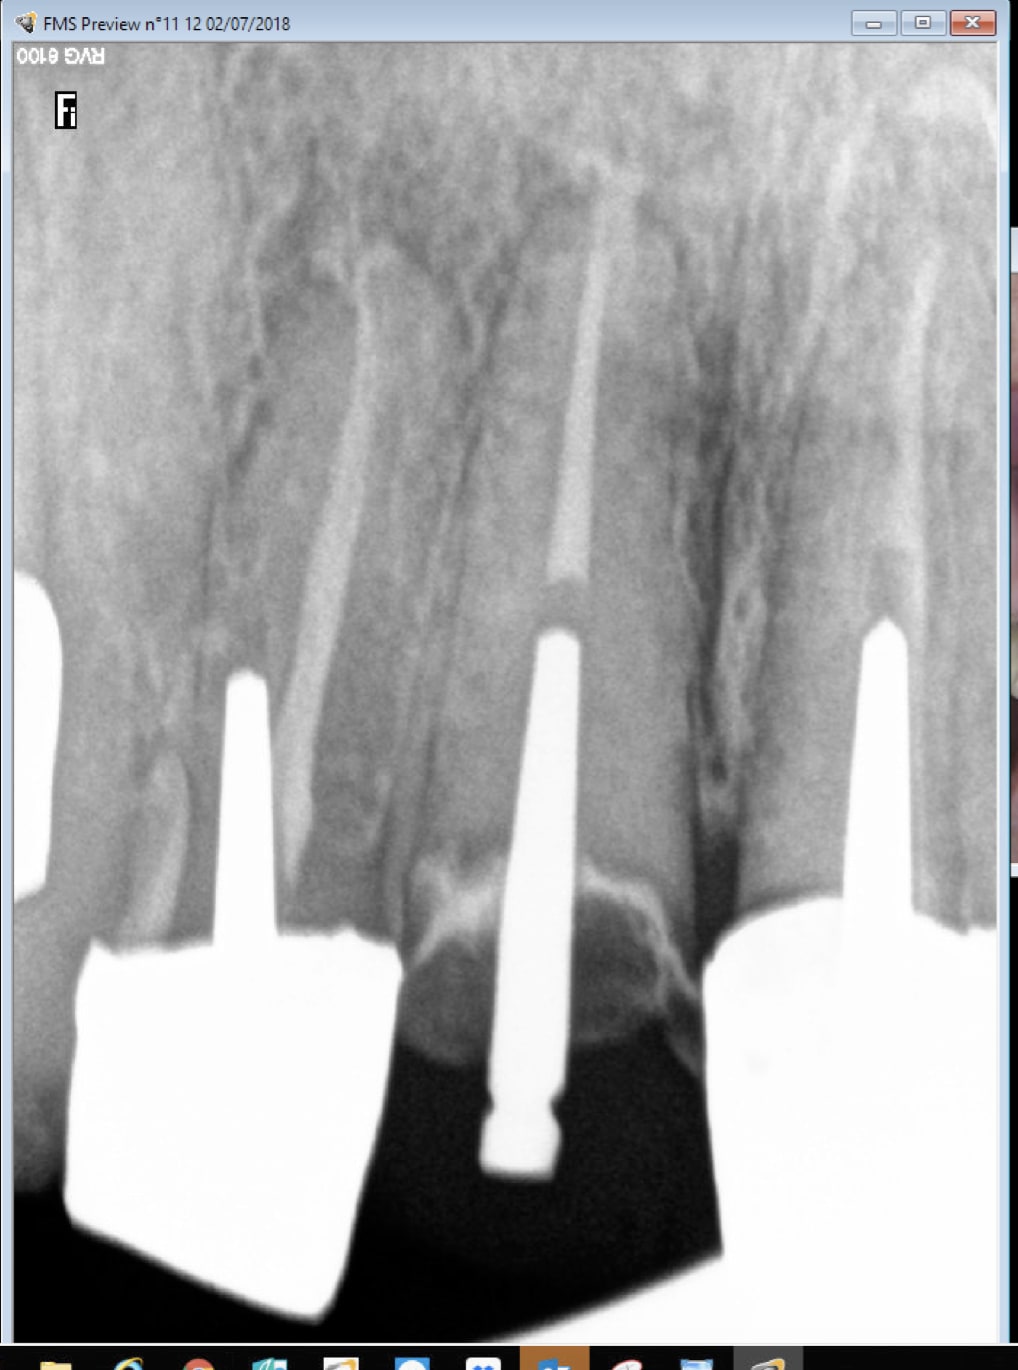

Tiiens par exemple radios recommandées dans ce cas ?

Capture d écran 2018 07 02 11.17 - Eugenol

Bilan TIB complet. -)))